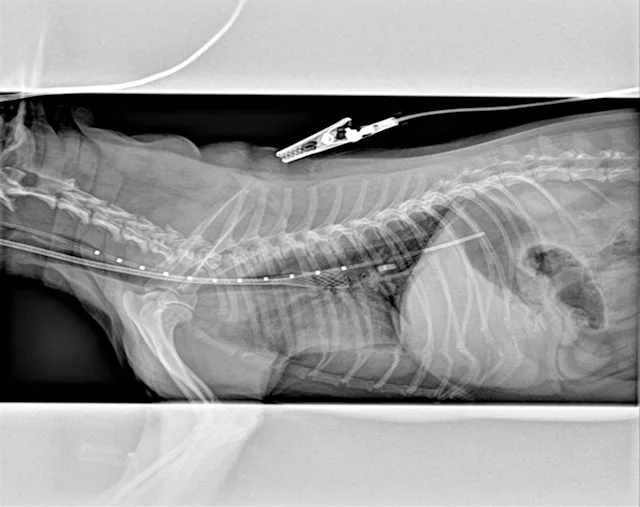

Definitive diagnosis is based on imaging (eg, survey radiography, fluoroscopy, ultrasonography, computed tomography, tracheobronchoscopy).13 Survey radiography should include dorsoventral and lateral views of the cervical region and thorax (Figure 1). Collapse of the trachea is best viewed in the cervical region during inspiration and in the intrathoracic region during exhalation.1 Radiography is critical to rule out conditions that may cause similar signs (eg, intrathoracic masses, pleural effusion) and cardiovascular abnormalities (eg, heart enlargement) that may complicate treatment. Radiography is noninvasive, cost effective, widely available, and can be performed without the risks associated with general anesthesia; however, false-positive results have been reported in 25% of dogs,14 and sensitivity ranges from 60% to 90%.2 In comparison, fluoroscopy allows direct viewing of tracheal motion during all phases of respiration, is noninvasive, and is very sensitive, although false-positive findings have also been reported with fluoroscopy.14 In one study, radiography underestimated the severity and frequency of collapse as compared with fluoroscopy.15

Lateral thoracic radiograph of a dog with tracheal collapse. The most severe area of collapse is just caudal to the thoracic inlet.